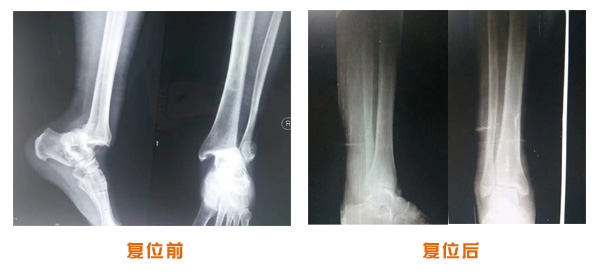

復位前后對比

尺橈骨骨折治療前后

尺橈骨克雷氏骨折治療前后